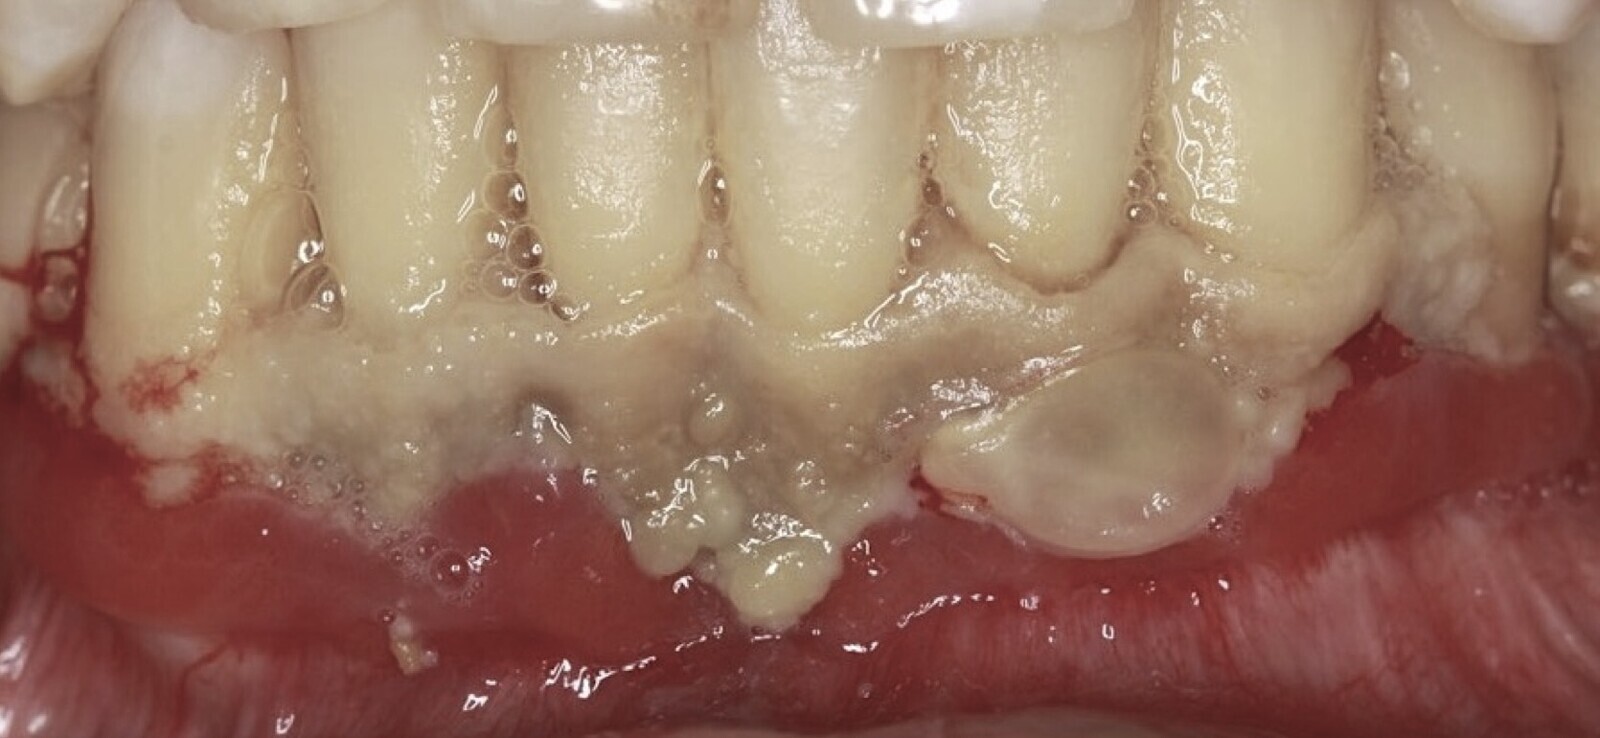

Figura 1. Osteonecrosis maxilar resultado de un tratamiento con un antiangiogénico (anticuerpo monoclonal).

La osteonecrosis de los maxilares relacionada con medicamentos MRONJ (por sus siglas en inglés) se caracteriza por la presencia de hueso expuesto o que puede ser sondado a través de una fístula intraoral o extraoral en la región maxilofacial, que persiste durante más de 8 semanas. Esta condición se observa en pacientes que han recibido tratamiento actual o previo con terapias antirresortivas, solas o combinadas con moduladores inmunológicos, o medicamentos antiangiogénicos, y que no tienen antecedentes de radioterapia o enfermedad metastásica en las mandíbulas[1].

Osteonecrosis maxilar resultado de un tratamiento con un antiangiogénico (anticuerpo monoclonal).